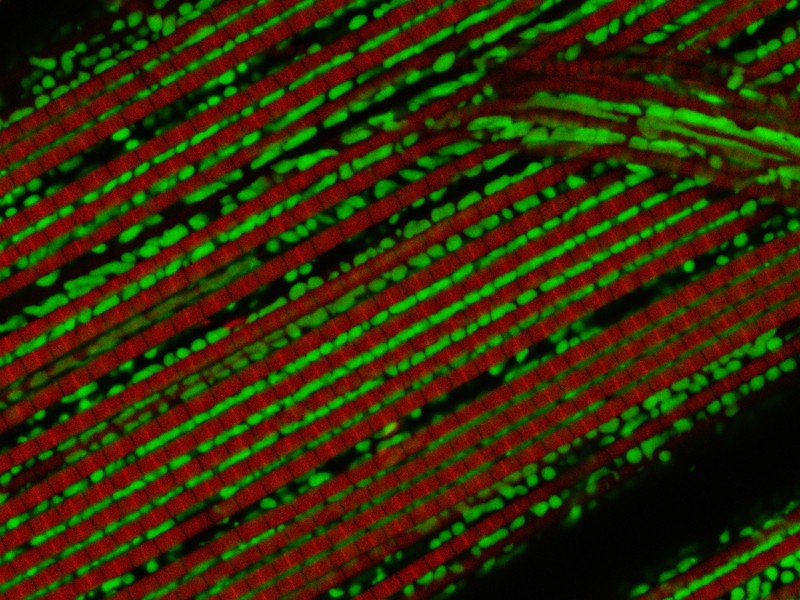

Das Gen PINK1 spielt eine Rolle bei der Parkinson-Krankheit. Wird das Gen in der Fliege ausgeschaltet, so werden die Mitochondrien (grün) geschädigt, worauf die Muskelfasern (rot) der Tiere zerfallen. Eine Aktivierung des Ret-Rezeptors, der beim Menschen den Wachstumsfaktor GNDF bindet, wirkt diesem Zerfall entgegen. [weniger]